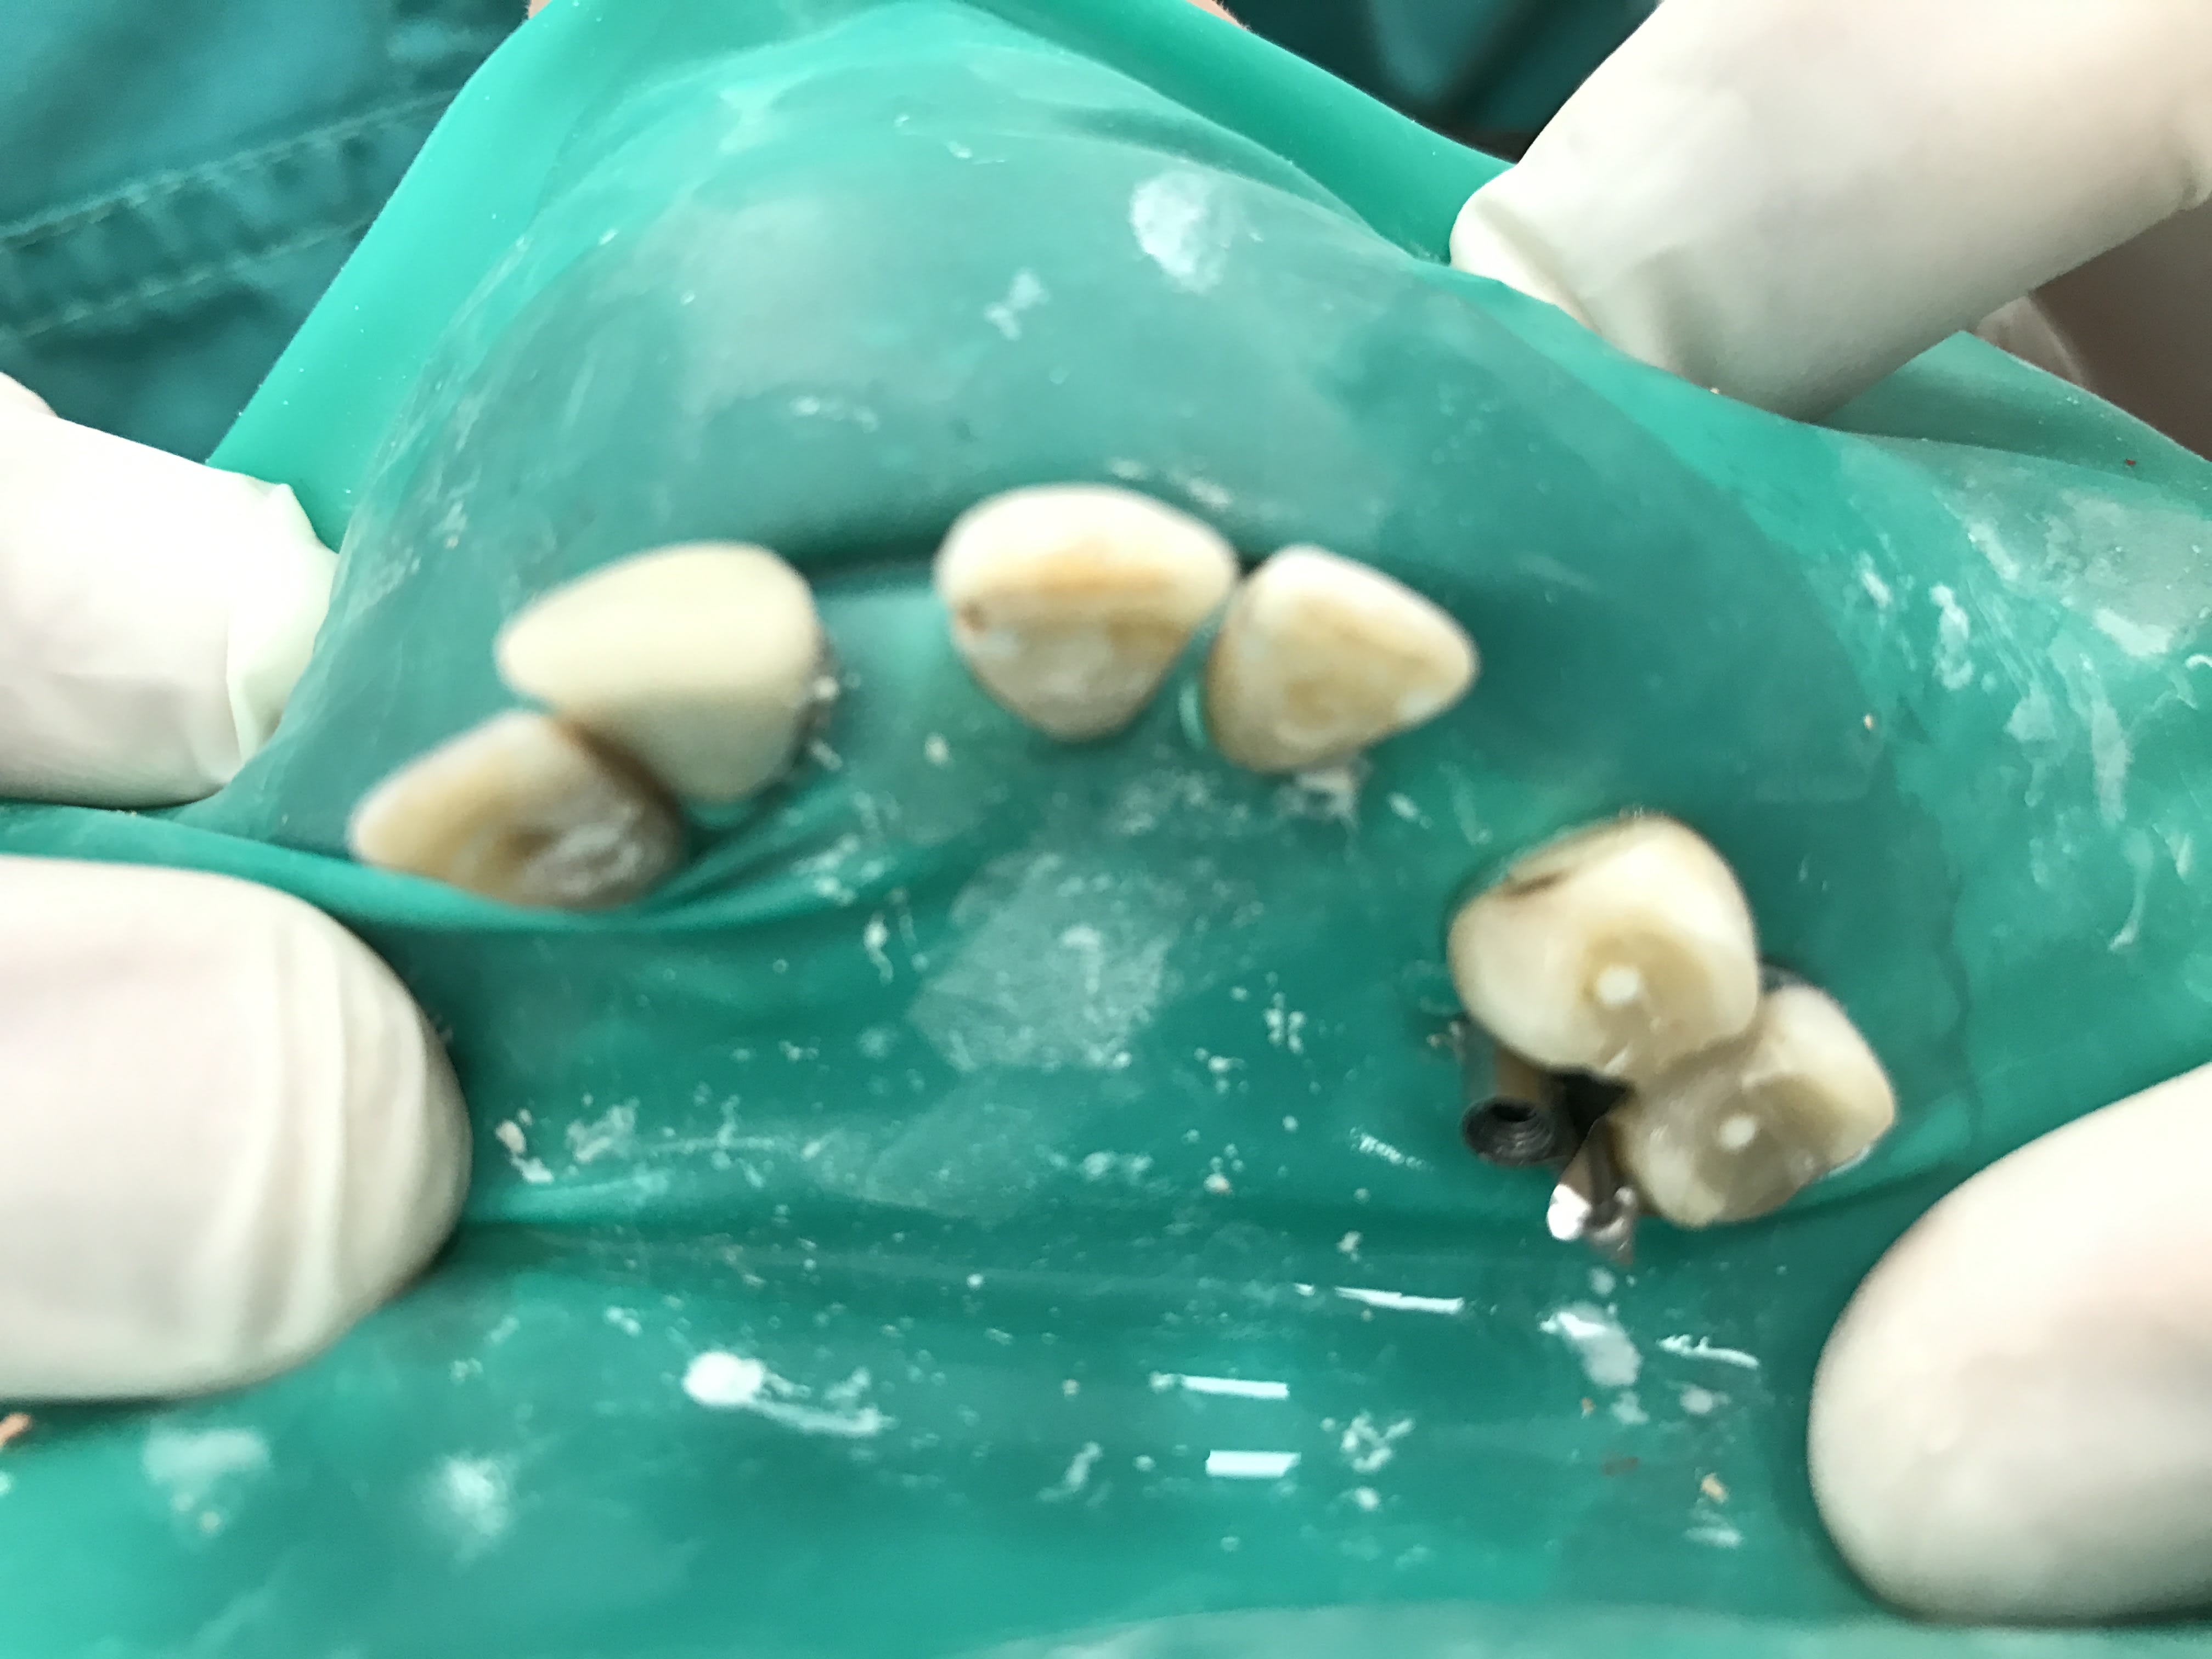

Bon et bien voila ou on en est aujourd'hui

Img 1461 odo6eo - Eugenol

Img 1452 fsszmf - Eugenol

Img 1443 yrolq8 - Eugenol

Img 1457 r2aopb - Eugenol

Img 1448 ekmmyu - Eugenol

iyaudat

31/07/2017 à 19h43

Les photos ne sont pas dans l'ordre je sais pas pourquoi.

Et bien voilà le patient en a pour son argent ... enfin la sécu.

Well done !

Y a plus qu'à tout passer au taille crayon ... ;) (j'imagine que tu n'as pas facturé de RTE?)

Effectivement pas facturé les rte...